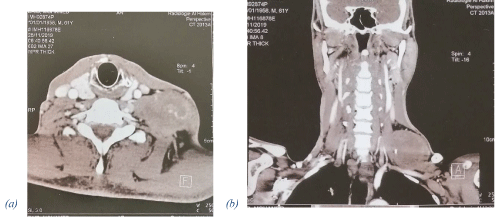

Brachial Plexus Schwannoma: Case Report

S.Touihmi*1 , H.Mimouni1 and I.Rkain2

Schwannomas, also known as neurinomas are benign, solitary nerve sheath neoplasm. When they occur in the head and neck, in 25–45 % ofcases,they usually develop in cranial nerves and the sympathetic chain with relative...